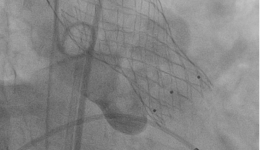

• “消失不见”的封堵器——山东大学齐鲁医院(青岛)成功完成我院首例生物可降解PFO封堵器植入

“消失不见”的封堵器——山东大学齐鲁医院(青岛)成功完成我院首例生物可...

近日,山东大学齐鲁医院(青岛)心内科在学科带头人钟敬泉教授、科室主任姚桂华教授、副主任由倍安教授的支持、指导下,孟庆峰副主任医师带领结构性心脏病团队与心超团队密切配合,结合超声和DSA两种影像技术,圆满完成我院首例生物可降解卵圆孔未...